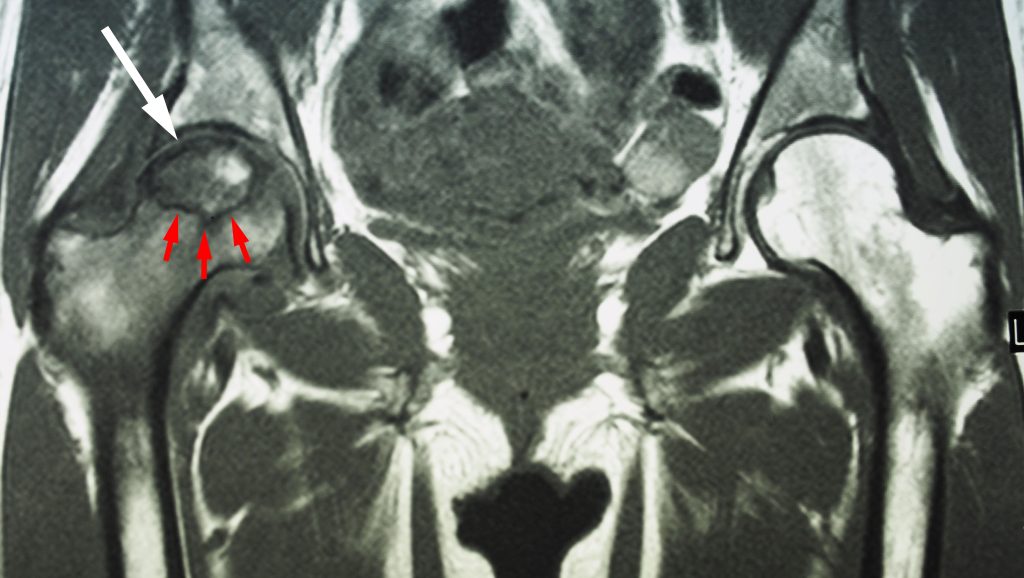

The MRI scan shows osteonecrosis in a patient’s right hip (white arrow). The dark line (red arrows) denotes the border between dead bone and living bone. The patient’s left hip is normal.